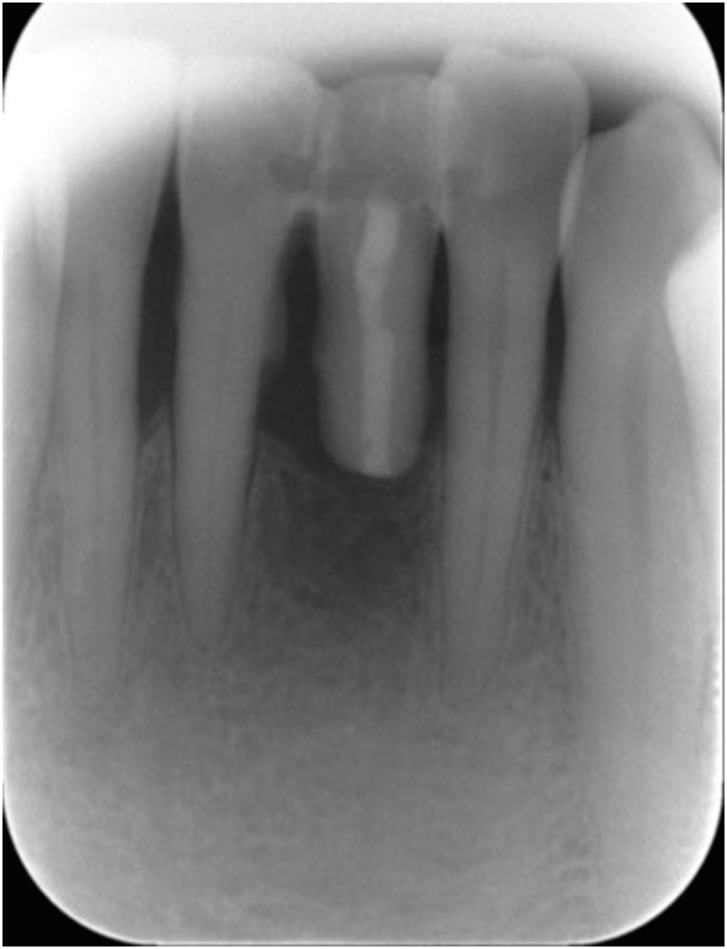

A 52-year-old man visited the Department of Conservative Dentistry because of mobility of the right mandibular central incisor (tooth #41) after it was smashed on a door 6 months previously. The tooth showed degree 3 mobility and slight tenderness on percussion. Clinical and radiographic examinations revealed that the tooth was root-fractured at the cervical third (Figure 1).

Figure 1

Preoperative view. (A) Intraoral photograph (labial view); (B) intraoral photograph (lingual view); (C) periapical view.